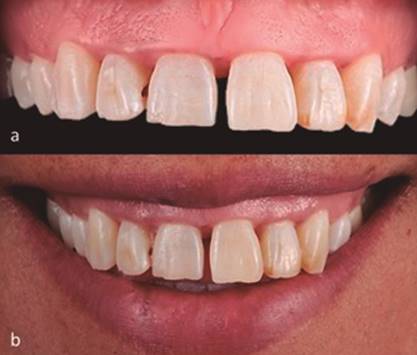

Paciente femenino de 38 años de edad, ASA I, aparentemente sana, sin antecedentes personales de relevancia y hábito de tabaquismo y toxicomanías negado, llegó en mayo del 2016 a la clínica de prótesis de la Escuela Nacional de Estudios Superiores unidad León de la UNAM con motivo de consulta “quiero arreglarme los dientes de adelante”. La paciente fue valorada protésicamente y se remitió al área de periodoncia para valoración periodontal, donde se obtuvo como diagnóstico periodontitis crónica generalizada moderada. Después de pasar por la fase I periodontal (eliminación de cálculo, así como raspado y alisado radicular) y de tener a la paciente en fase de mantenimiento (Figura 1), se valoró para alargamiento de corona estético que abarcara del segundo premolar superior derecho al segundo premolar superior izquierdo (15-25) para posterior rehabilitación protésica. Radiográficamente se observó una porción corona-raíz y altura adecuada de hueso alveolar (Figura 2a y 2b). A la inspección clínica se observó diastema en los centrales superiores, pérdida de papilas, discrepancia de los márgenes gingivales en la zona anterosuperior y un biotipo gingival grueso (Figura 3a), al igual que una línea de sonrisa alta (Figura 3b). Según las condiciones de la paciente y las consideraciones para realizar un alargamiento de corona, se decidió que el procedimiento era viable. El área de prótesis realizó la guía quirúrgica (mock up) según el encerado diagnóstico y análisis de sonrisa digital diseñado.